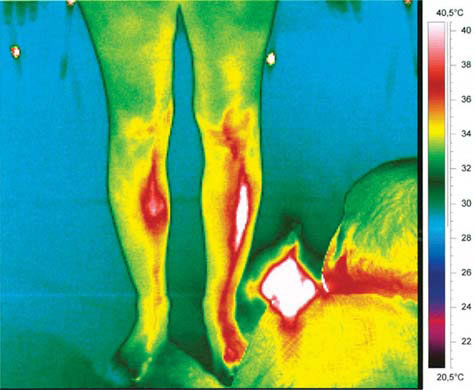

This study shows, for the first time, evidence of the existence of the acupuncture meridian structure in the human body. After moxibustion (or similar light stimulation) of the body in the 3-5 microm range, "light channels" appear on the body, which appear to be identical to what are known as meridians in all textbooks of Traditional Chinese Medicine. These findings appear not only to confirm the existence of acupuncture meridians, but they also open a new window on understanding the energy transfer dynamics of the human body. Furthermore, it is likely that living matter is not in the ground state, but permanently electronically excited.

BACKGROUND: According to Traditional Chinese Medicine (TCM) the vital energy flows through a system of channels also called meridians. Generally accepted proof for meridians cannot be considered as being given. Goal of this study was to examine whether possible stimulation-induced meridian-like structures, as recently described by other authors, can be visualized and objectified simultaneously at different infrared wavelength ranges. METHODS: The study analyses evidence for the existence of acupuncture-specific, meridian-like artifacts in 6 healthy volunteers (mean age +/- SD 28.7 +/- 3.7 years; range 25 - 35 years). Two infrared cameras at different wavelength ranges were used for thermographic control of possible stimulation effects (moxibustion-cigar, infrared warmth stimulation, needle and laserneedle stimulation). In addition to thermography, temperature and microcirculatory parameters were registered at a selected point using laser-Doppler flowmetry. RESULTS AND CONCLUSION: After moxibustion (or infrared light stimulation) of the body at 2 - 5 microm and 7.5 - 13 microm ranges, different structures appear on thermographic images of the human body which are technical artifacts and which are not identical to what are known as meridians in all textbooks of TCM. Further scientific studies are required regarding the possible visualization of meridians.